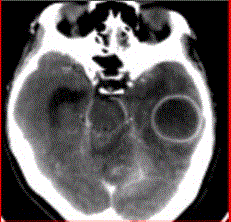

问题 患者女,26岁,头痛、低热10d余,既往有左侧慢性中耳炎病史。CT表现如下图。 脑脓肿的MRS表现,正确的是

选项 A.Cho明显升高 B.NAA未见异常 C.Lac升高 D.乙酸峰、乳酸峰、丁二酸峰升高 E.Lip峰升高

答案 D